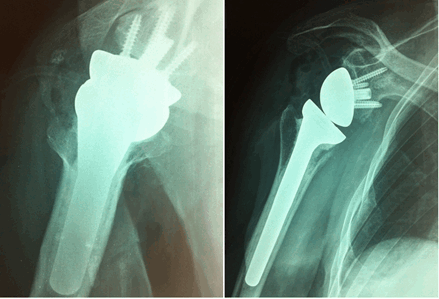

Пациенту имплантирован реверсивный эндопротез плечевого сустава Delta Xtend фирмы DePuy (рис. 5).

Рис. 5. Рентгенограммы пациента после оперативного лечения в прямой и аксиальной проекции (второй случай)

Послеоперационное гистологическое исследование удаленных тел подтвердило диагноз вторичного синовиального хондроматоза. В отдалённом периоде после операции, через 2 года, пациент активно жалоб не предъявляет, функция правого плечевого сустава восстановилась полностью, пациент вернулся к ежедневной бытовой и профессиональной деятельности (рис. 6).